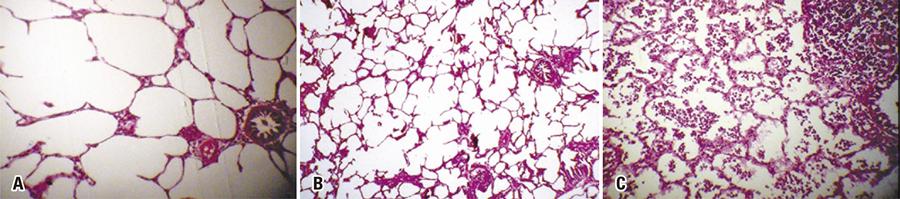

Experimental study with 25kg Landrace pigs submitted to a longitudinal cervico-thoraco-abdominal incision for exposure of the trachea, thorax and abdomen. The tissues were frozen by continuous spray application at different periods of time (5, 10 and 15 seconds). Spray cryotherapy was performed using a fluorinated gas (tetrafluorethane) delivered at – 47°C temperature (DermaFreeze®, Emdutos; ANVISA registration 80409950001; price R$ 394,00). via an adapted, disposable 1.8mm cholangiography catheter (Olympus; price R$ 280,00). The specimens were resected for histopathological analysis.

Thirty samples were obtained from ten different organs and divided according to spray cryotherapy application time. System activation for 5, 10 or 15 seconds led to consumption of 14g, 27g and 40g of gas respectively (average gas consumption, 2.7g/s using a 1.8mm catheter). The system comprising a spray tube and catheter proved user-friendly and effective, with constant gas dispersion and adequate tissue freezing. In spite of effective freezing, microscopy failed to reveal tissue changes. This may have reflected methodological constraints precluding evaluation at tissue damage peak time (48 hours).